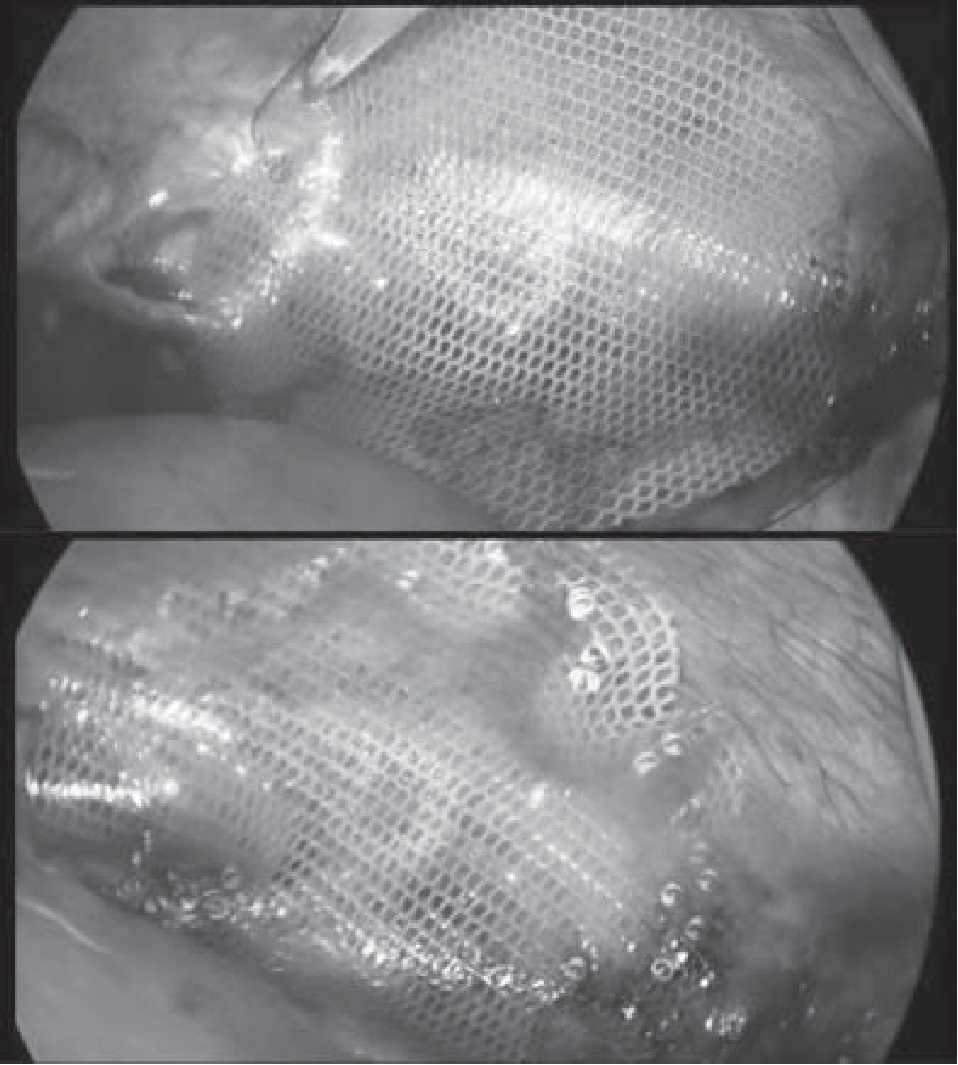

Под комбинированной анестезией доступом по Хассену установлен оптический троакар. Создан карбоксиперитонеум величиной в 12 мм рт. ст. Выпота в брюшной полости нет. В брюшной стенке установлено 4 рабочих лапаропорта. При ревизии брюшной полости выявлен умеренно выраженный спаечный процесс в верхних отделах. Выполнен адгезиолизис. Визуализирован грыжевой дефект левого купола диафрагмы, в котором расположены дно желудка и селезенка. Низвести селезенку не представилось возможным. Для решения данной проблемы было принято решение воспользоваться имеющимся рубцом после люмботомии по поводу вскрытия и дренирования абсцесса левой почки. Была использована методика «hand-assistant», при которой в брюшную полость вводится рука хирурга с целью выполнения определенных манипуляций, которые невозможно осуществить только лишь с помощью лапароскопических инструментов, после чего селезенка свободно низведена в брюшную полость. Произведены мобилизация грыжевого мешка и дренирование плевральной полости слева в VII межреберье по среднеподмышечной линии, после чего края грыжевого дефекта свободно сведены и ушиты одиночными узловыми швами. С учетом истонченных стенок грыжевых ворот со склонностью к прорезанию, установлен сетчатый эндопротез с покрытием (Symbotex), который фиксирован эндогерниостеплером ProTack (рис. 2). Для более надежной фиксации сетчатый эндопротез дополнительно закреплен узловыми швами. В брюшной полости установлено два дренажа, один из которых – в левый боковой канал, а второй – в малый таз.

Рис. 2. Интраоперационная картина сетчатого эндопротеза, фиксированного с помощью эндогерниостеплера